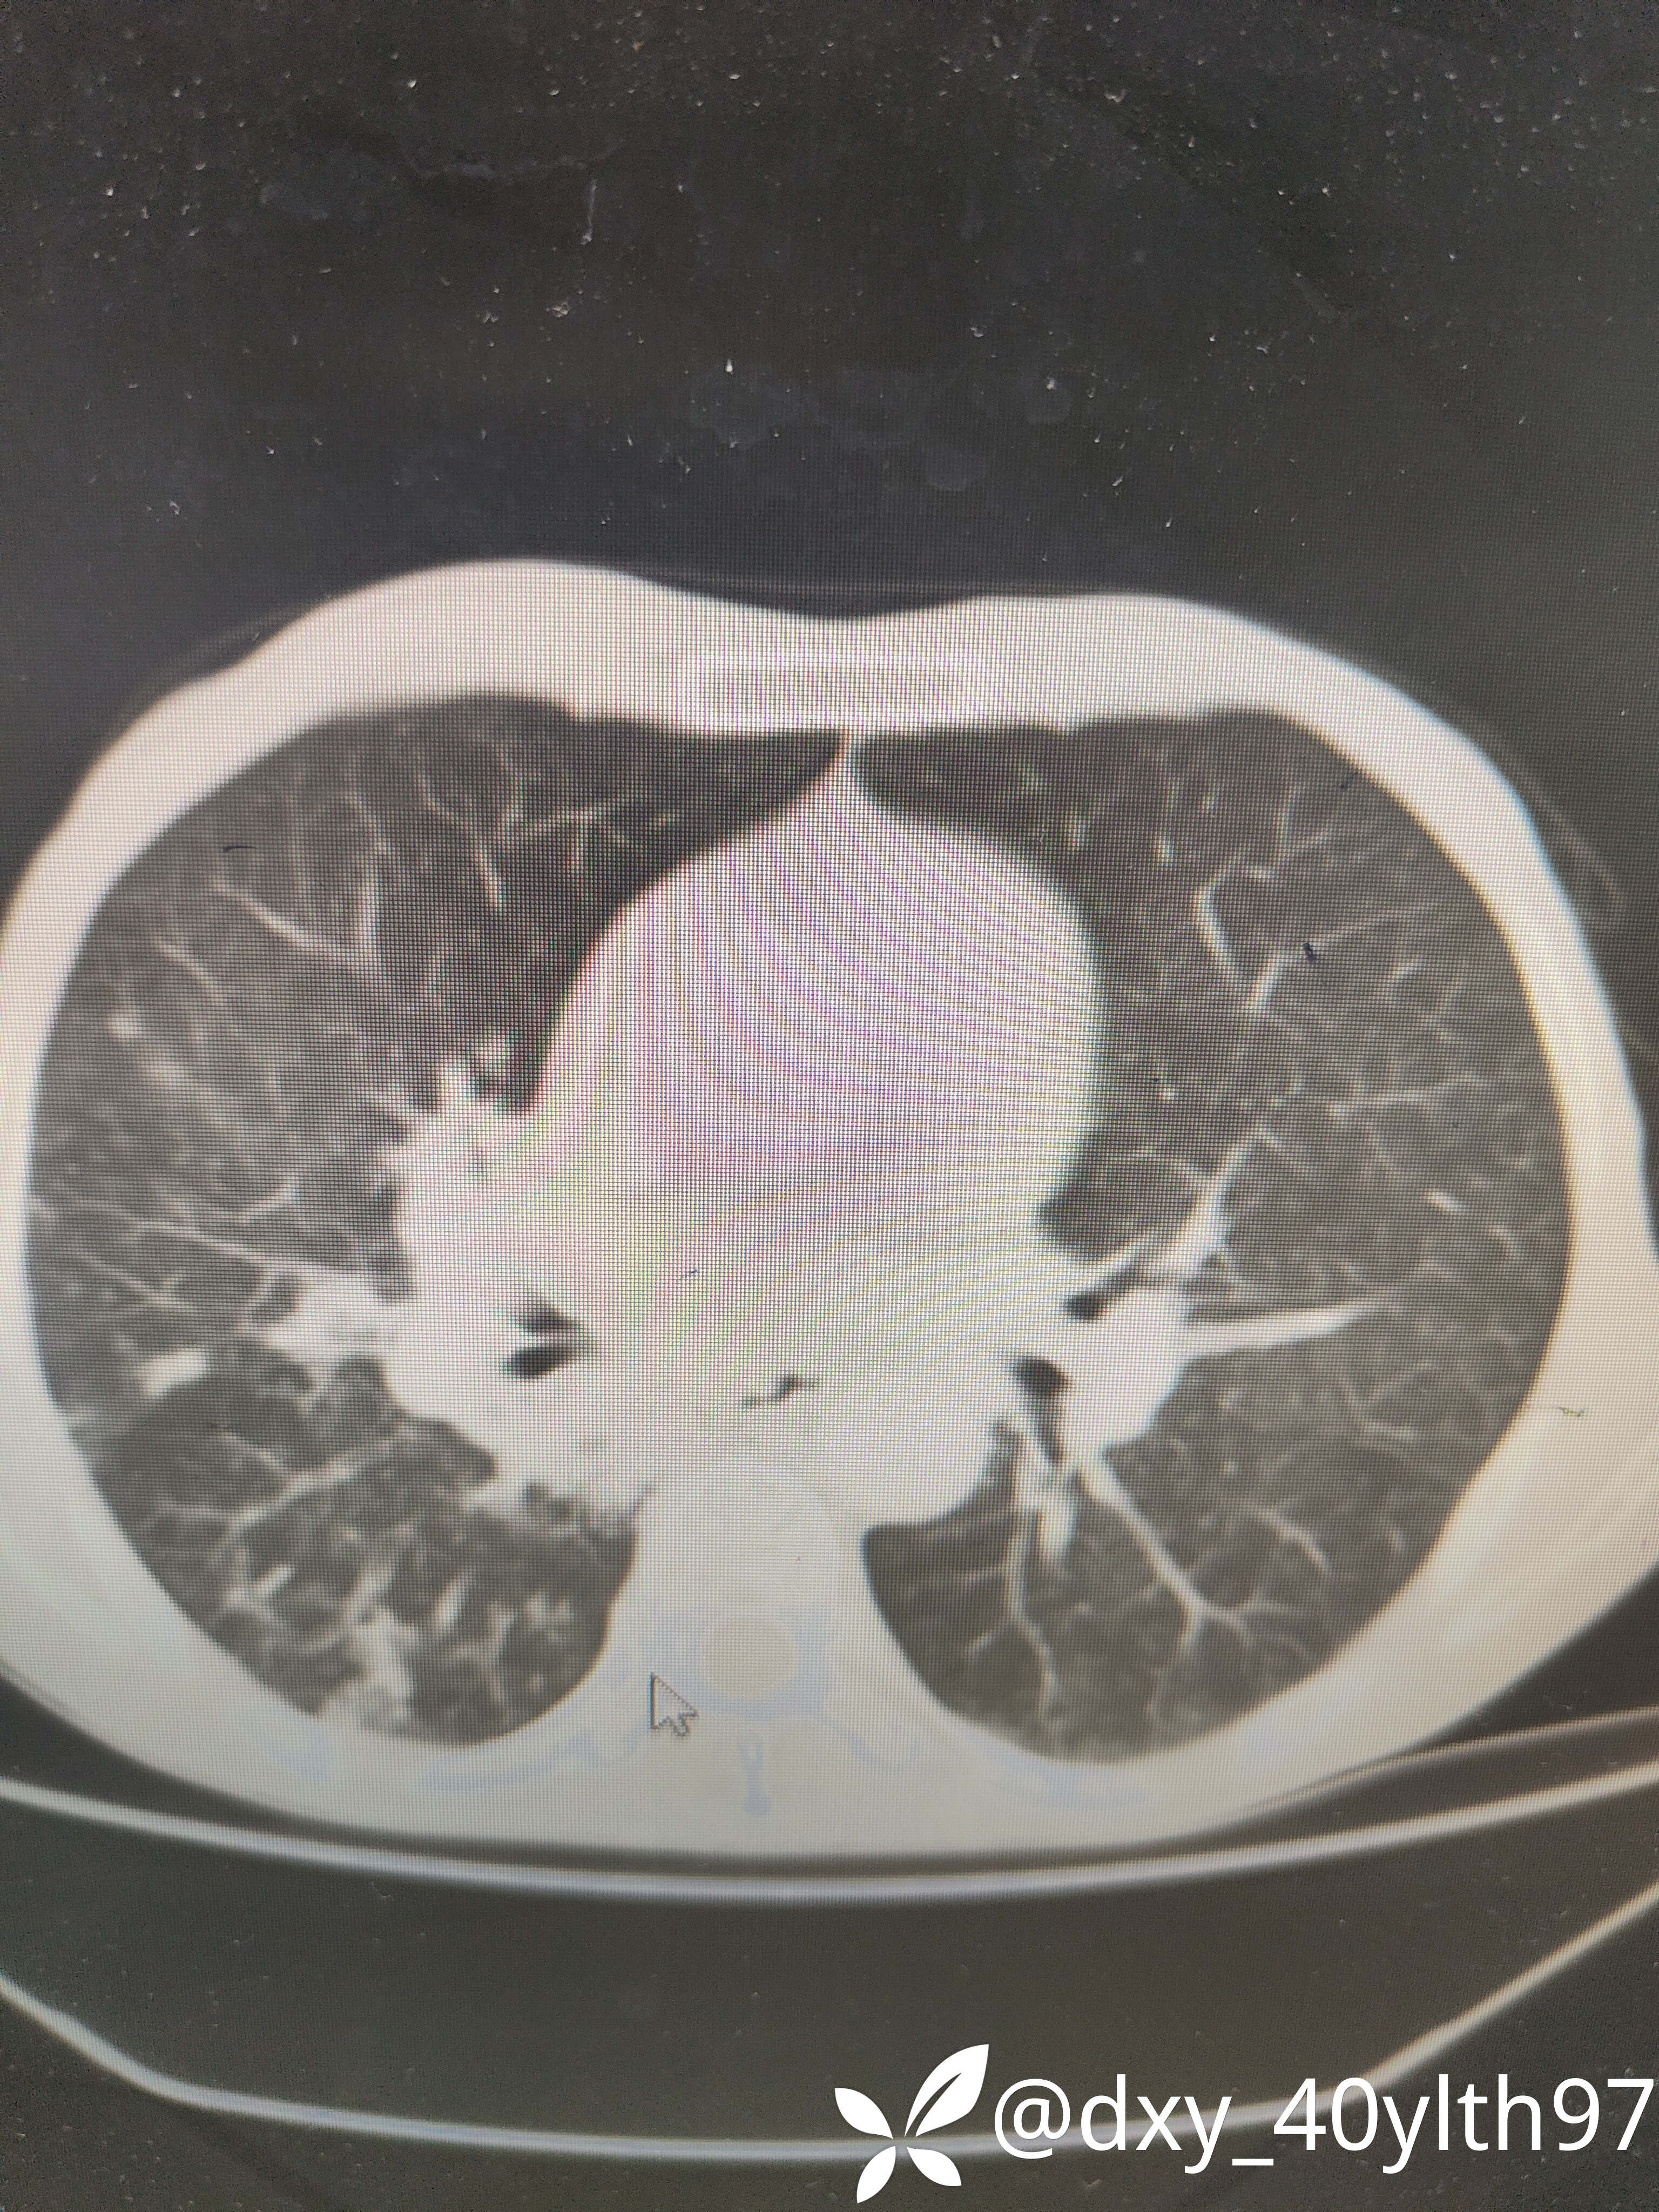

治疗经过:2023-8月入院后查肺部CT平扫

2023年8月肺部CT平扫影像结果提示:1.右肺上叶密度增高影较前显著增大,建议进一步检查;2.两肺多发斑片结节灶较前增多,部分增大。

肺部增强CT影像学提示:右肺内大片不规则影轻度强化,肿瘤可能。